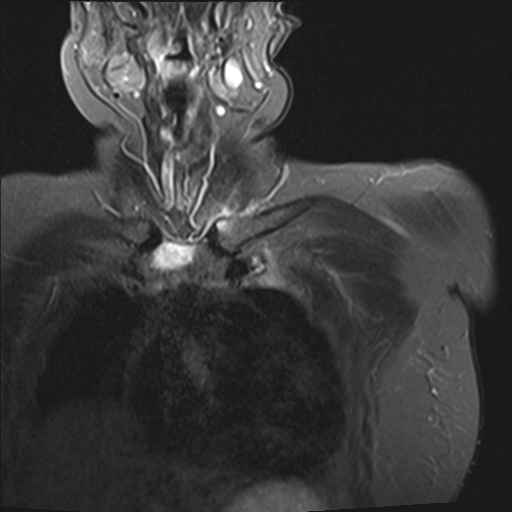

50 yr female was presented with neck and interscapular pain and was referred for MRI covering cervical spine and scapular region. On basis of findings on initial findings, patient was recalled for further MRI imaging.

What are the imaging findings and diagnosis?